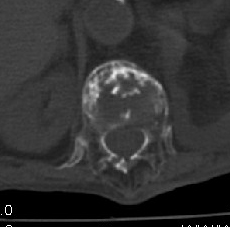

男:89岁因外伤后2天行ct检查。请各位战友讨论图中所指是否是骨折和形成该影像的原因(扫描层面位于椎体中份)。

老年性骨质疏松,椎体前缘出现双边征支持压缩骨折。椎体骨质稀疏,似有破坏,警惕溶骨性骨转移。

椎体前缘双边征,其后椎体内密度增高均提示压缩性骨折

压缩性骨折,骨质疏松,前缘密度增高,考虑压缩所致

椎体前缘呈双边征 考虑 压缩性骨折,椎体退行性病变。

我的报告1:腰椎骨质退行性改变。

2:t12改变考虑压缩骨折?请结合临床。

骨质疏松,考虑陈旧压缩性骨折.(有硬化边).